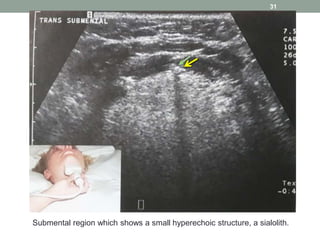

Submental region which shows a small hyperechoic structure, a sialolith.

31 Submental region whichshows a small hyperechoic structure, a sialolith.